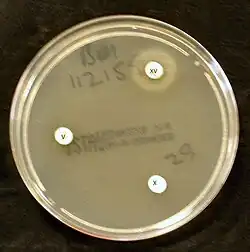

Bacterial culture of H. influenzae is performed on agar plates. The strongest growth is seen on chocolate agar at 37 °C in a CO2-enriched incubator.[33] The ideal CO2 concentration for the culture is ~5%.[34] However adequate growth is often seen on brain-heart infusion agar supplemented with hemin and nicotinamide adenine dinucleotide (NAD)

Colonies of H. influenzae appear as convex, smooth, pale, grey, or transparent colonies with a mild odor.[34] H. influenzae will only grow on blood agar if other bacteria are present to release these factors from the red blood cells, forming 'satellite' colonies around these bacteria. For example, H. influenzae will grow in the hemolytic zone of Staphylococcus aureus on blood agar plates; the hemolysis of cells by S. aureus releases NAD which is needed for its growth. H. influenzae will not grow outside the hemolytic zone of S. aureus due to the lack of nutrients in these areas.[35]